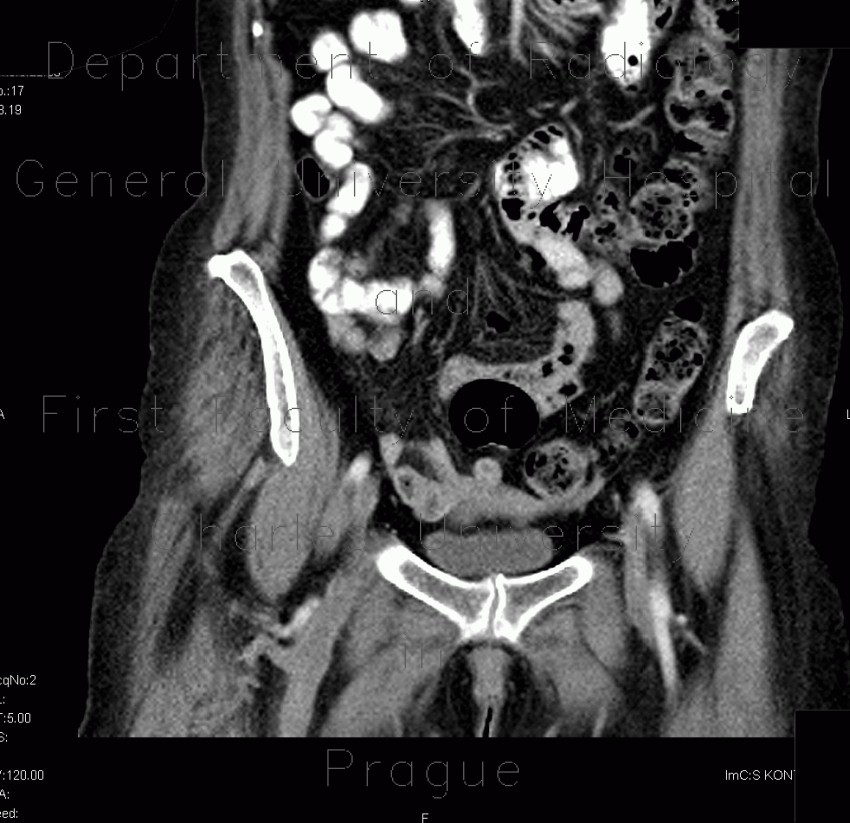

Thoracic aortic aneurysm - Wikipedia, The Free Encyclopedia

A thoracic aortic aneurysm is an aortic aneurysm that presents primarily in the thorax. The diagnosis of thoracic aortic aneurysm usually involves patients in their 60s and 70s. Risk factors Edit. Hypertension and cigarette smoking are the most important risk factors, ... Read Article